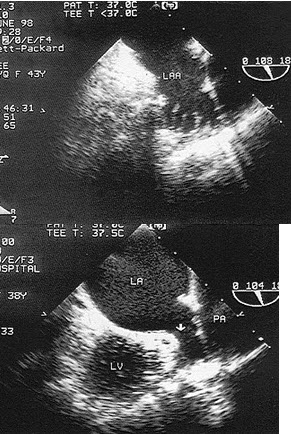

C.70%

某患者舒张期二尖瓣口心动图所示,提示()

A.二尖瓣狭窄

B.二尖瓣关闭不全

C.二尖瓣脱垂

D.正常声像图

E.二尖瓣赘生物